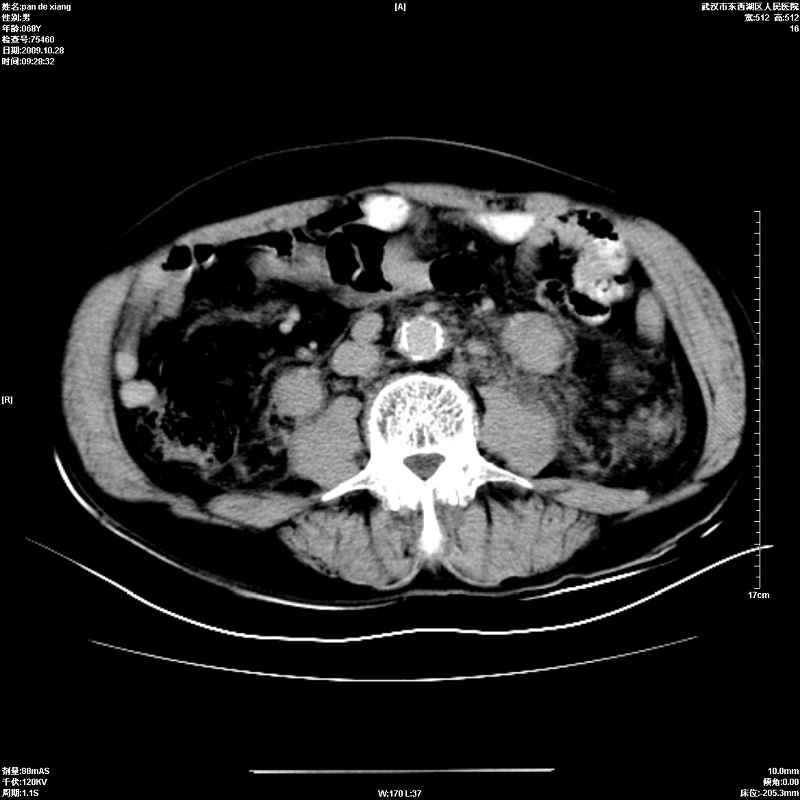

以下是引用杀毒软件在2009-10-28 20:41:00的发言:[br]结合临床考虑---白血病双肾改变或淋巴瘤。

以下是引用zxl51642在2009-10-29 9:59:00的发言:[br]结合临床“单克隆免疫球蛋白血症”,考虑双肾为继发损害并肾功能不全(尿中大量igg及少量iga、igm等大分子免疫球蛋白滤出所致继发损害),椎前软组织肿块为髓外造血。与浆细胞瘤有区别,平扫时有战友说的很清楚。